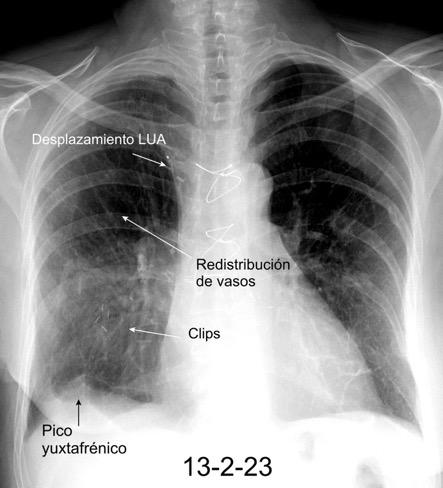

Parálisis frénica transitoria tras cirugía de válvula aórtica

Parálisis frénica transitoria post cirugía cardiaca (10%).

Puede acompañarse de atelectasia del LII.

Benjamin JJ et al. . Left lower lobe atelectasis and consolidation following cardiac surgery: the effect of topical cooling on the phrenic nerve. Radiology 1982